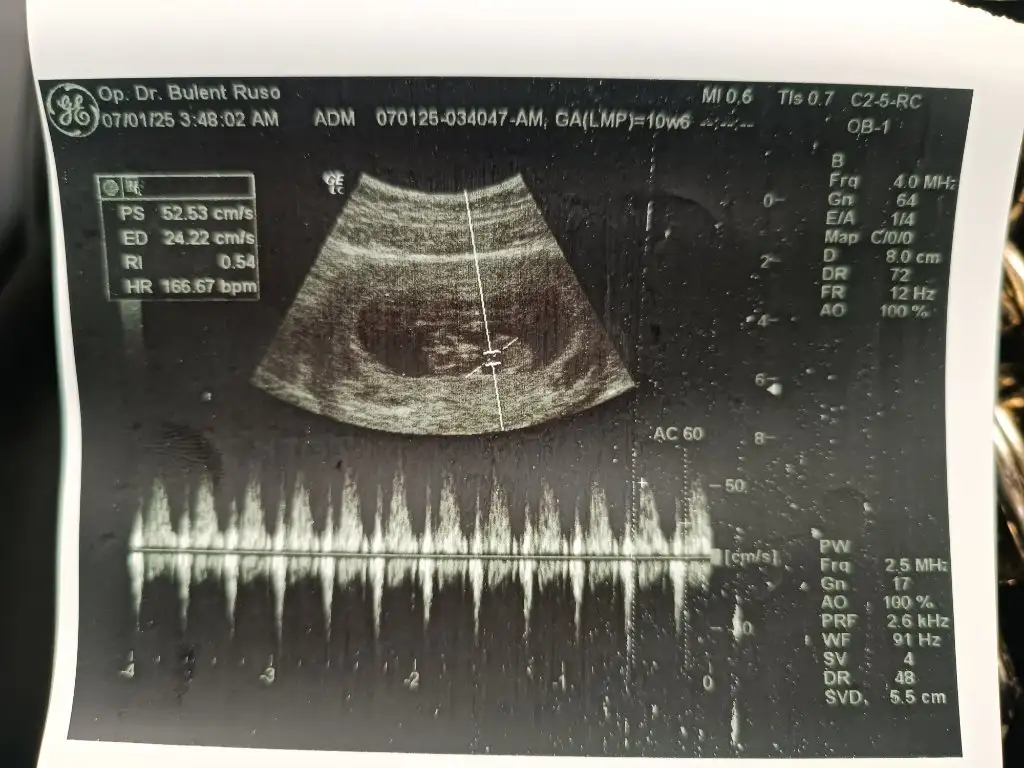

Kızlar hayırlı bereketli cumalar olsun inşallah. Az evvel doktordan geldim ense kalınlığı 2.2 dedi üçe kadar normal sayılabilir ama buda biraz yüksek dedi burun kemiği görünüyo dedi fetal DNA önerdi. Şuan 12+1 im ultrason fotoğrafını atıyorum şimdi hem fikir hemde cinsiyet tahmini almak istiyorum sizlerden,

Eklentiler

• 17358965762895763360544556751194.webp

45,1 KB · Görüntüleme: 115